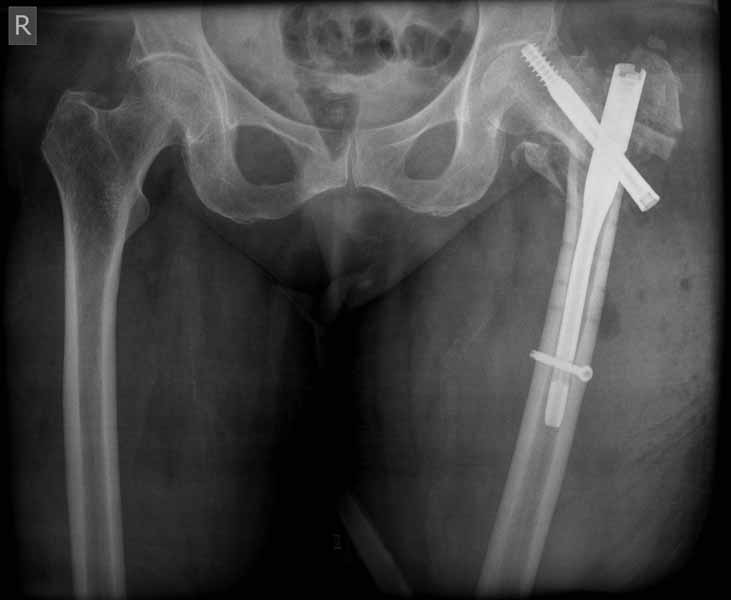

Сеньоры-пэры ревизировали гвоздем, шуруп поставили по той же дорожке, только поглубже. Да еще и bone graft не пожалели. "Результат" уже был через 2 дня.

Если сохранять головку - думаю надо было в валгусе фиксировать перелом гвоздем, или DCS, т.к. все-равно разрезали, чтоб достать DHS.

Как фиксировать дальше?